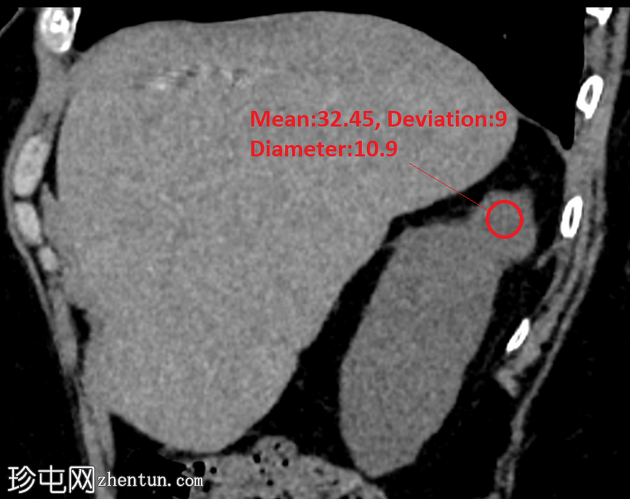

矢状位平扫

5.png

右肾后上极可见2.8 cm外生性强化病灶,提示肾细胞癌(RCC)。右肾静脉和下腔静脉通畅。未见明显局部淋巴结肿大。右肝叶可见高密度金属影。可见含脂肪的脐疝。